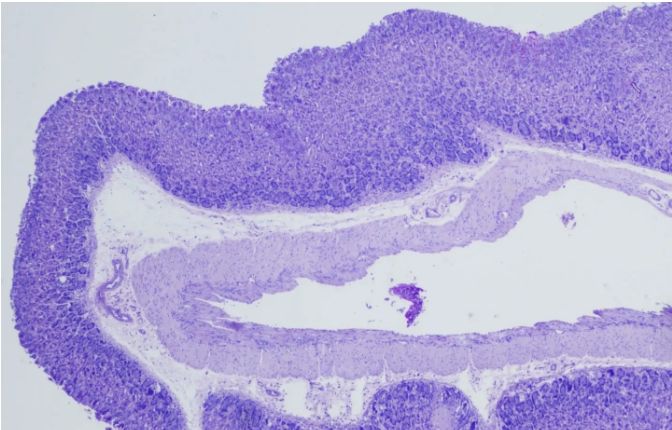

[圖1]

首先,我們需要了解PAS染色的基本原理——過碘酸能夠氧化組織中的多糖類物質(zhì),使其形成醛基或酮基。隨后,雪夫試劑與這些醛基或酮基發(fā)生反應(yīng),生成不溶于水的有色化合物,從而在顯微鏡下呈現(xiàn)出特定的顏色。這種顏色反應(yīng)不僅具有高度的特異性,而且敏感性也很高,能夠準確反映組織中多糖類物質(zhì)的分布和含量。

一、染色強度和分布

染色強度的深淺可以反映組織中多糖類物質(zhì)的含量。一般來說,染色越深,說明多糖類物質(zhì)含量越高;反之,染色越淺,則含量越低。同時,我們還需觀察染色的分布情況,以了解多糖類物質(zhì)在組織中的具體位置和形態(tài)。